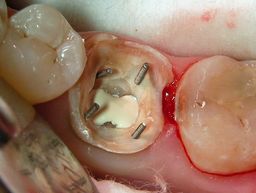

Zur Verankerung werden kleine Schrauben (Dentinstifte) in das verbleibende Dentin eingedreht. Sie ragen aus dem Zahn heraus und geben der Aufbaufüllung zusätzlichen Halt. Als Aufbaumaterial bewährt sich Amalgam durch seine sichere Verarbeitung und Festigkeit (1).

Das Aufbaumaterial wird schichtweise eingebracht und zwischen den Stiften kondensiert. Ziel ist eine geschlossene, ausreichend hohe Zahnwand, die später der Kofferdamklammer Halt gibt.